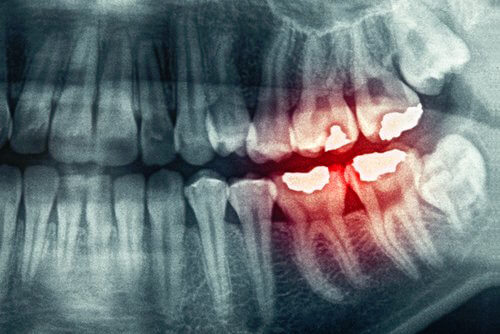

Le bruxisme est un problème qui affecte plus de gens que nous le pensons. Il consiste à serrer les dents ou les mâchoires. Dans les cas les plus extrêmes, une attelle de décharge est habituellement utilisée. Si elle n’est pas utilisée, cela peut causer une usure importante des dents.

La tension qui se manifeste lorsque vous serrez la mâchoire vous fera mal à la tête le matin. Ceci est le résultat du stress, de l’inquiétude, de l’anxiété ou de la dépression. Parfois, même l’utilisation d’une attelle ne nous empêche pas d’avoir mal à la tête.

L’idéal dans ces cas est non seulement de consulter un dentiste qui nous fournit une attelle qui protège nos dents, mais aussi un psychologue. Il est important de savoir d’où vient toute la tension, ce à quoi nous pensons la nuit en grinçant des dents.